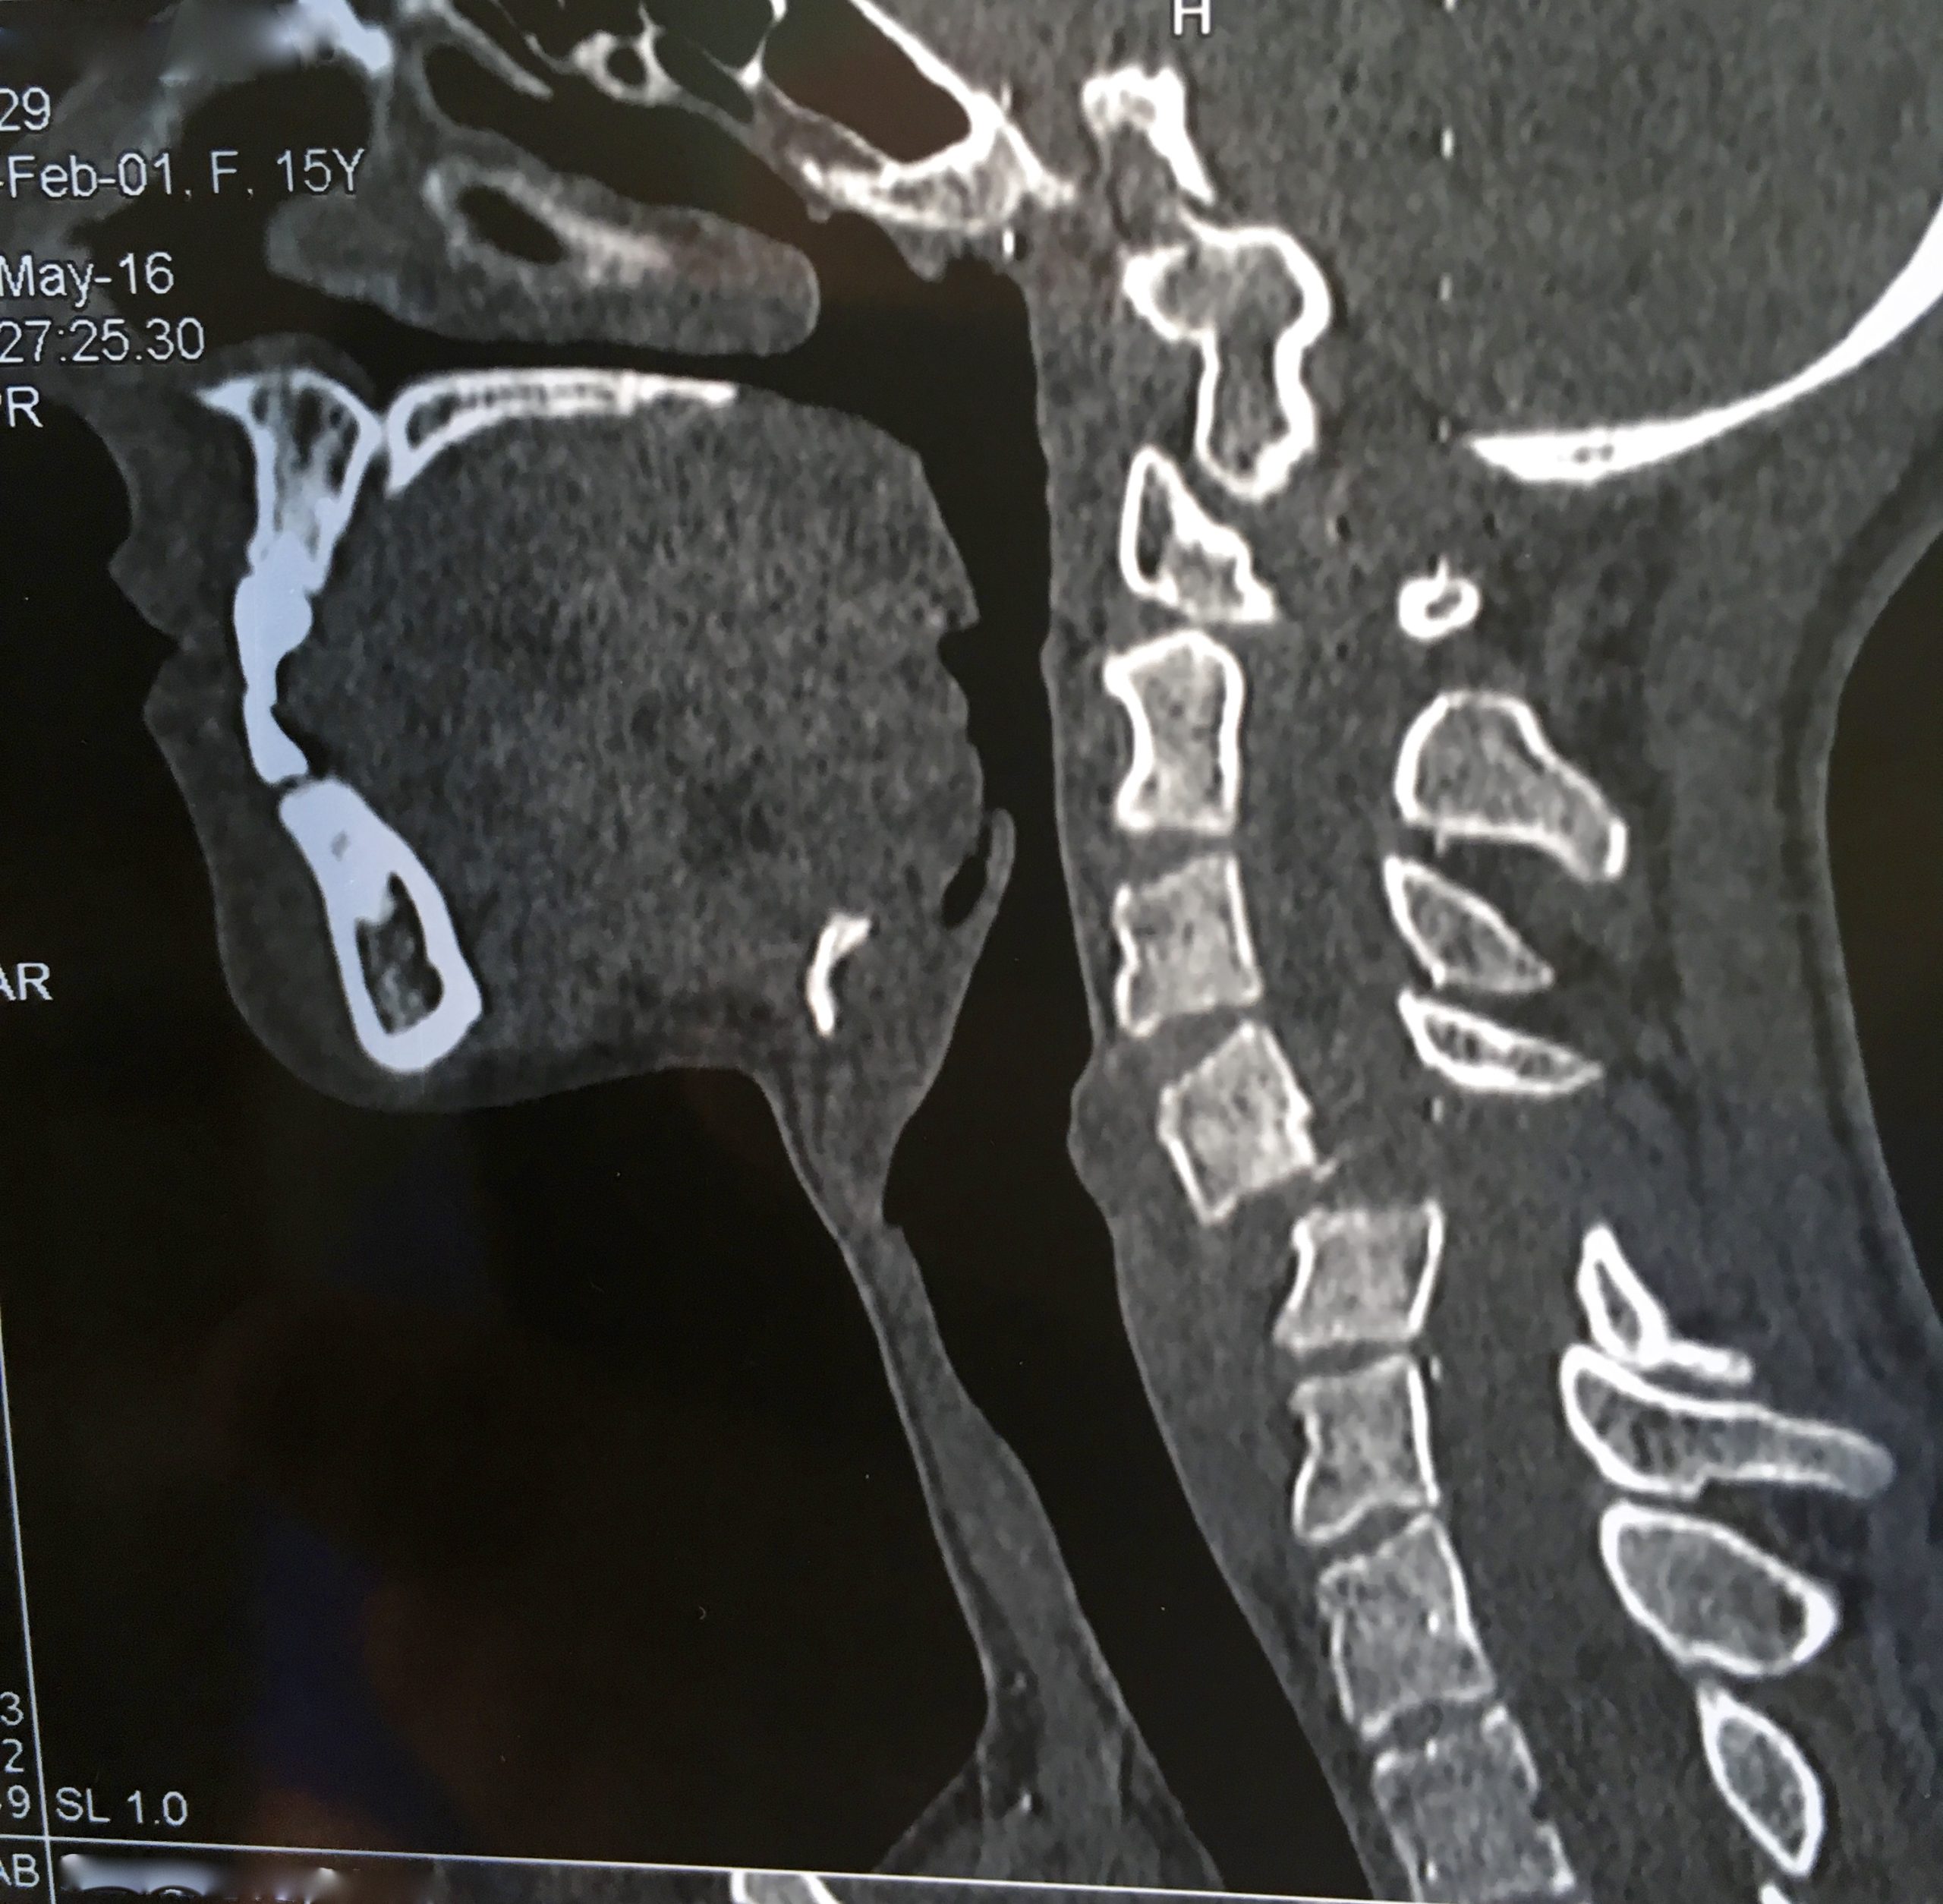

Види деформацій залежать від конкретної ділянки хребта, де відбуваються дегенеративні процеси — шийного, грудного або поперекового відділів хребта. Наявність або відсутність ускладнень, зокрема пролежнів та травм спинного мозку, відіграє важливу роль у визначенні ступеня посттравматичної деформації.

Клінічна картина патології

Головна ознака розвитку посттравматичних деформацій хребта – біль, що відчувається пацієнтом у спині, а пік її прояву спостерігається у тому відділі, де відбувається патологічний процес. Згодом пацієнт, у якого больовий синдром слабо виражений, тому залишається без належної уваги, починає відчувати труднощі в рухах, які стають дедалі скутішими і призводять до посилення болю.

Не виключається поява спастики у кінцівках. При деформації грудного відділу хребетного стовпа можуть виникнути проблеми з диханням, порушується робота серцево-судинної системи.

Через больовий синдром людина не може протягом тривалого часу утримувати хребет у вертикальному положенні. З розвитком патології біль посилюється і стає яскраво вираженим. Під час клінічного огляду спостерігається напруга паравертебральної мускулатури.

Посттравматичні деформації хребта неминуче призводять до порушення роботи інших органів прокуратури та систем, особливо страждає центральна нервова система. Ситуація може посилюватися стисненням спинного мозку, внаслідок чого виникають незворотні процеси неврологічного характеру.

У більшості випадків у пацієнта спостерігаються порушення функції сечостатевої системи, парези і паралічі в кінцівках. При деформації у шийному відділі хребта пацієнт може відчувати часті головні болі, зниження гостроти зору. Якщо зачеплений спинний мозок, виникають важкі патології, які без надання своєчасного лікування мають незворотний характер.